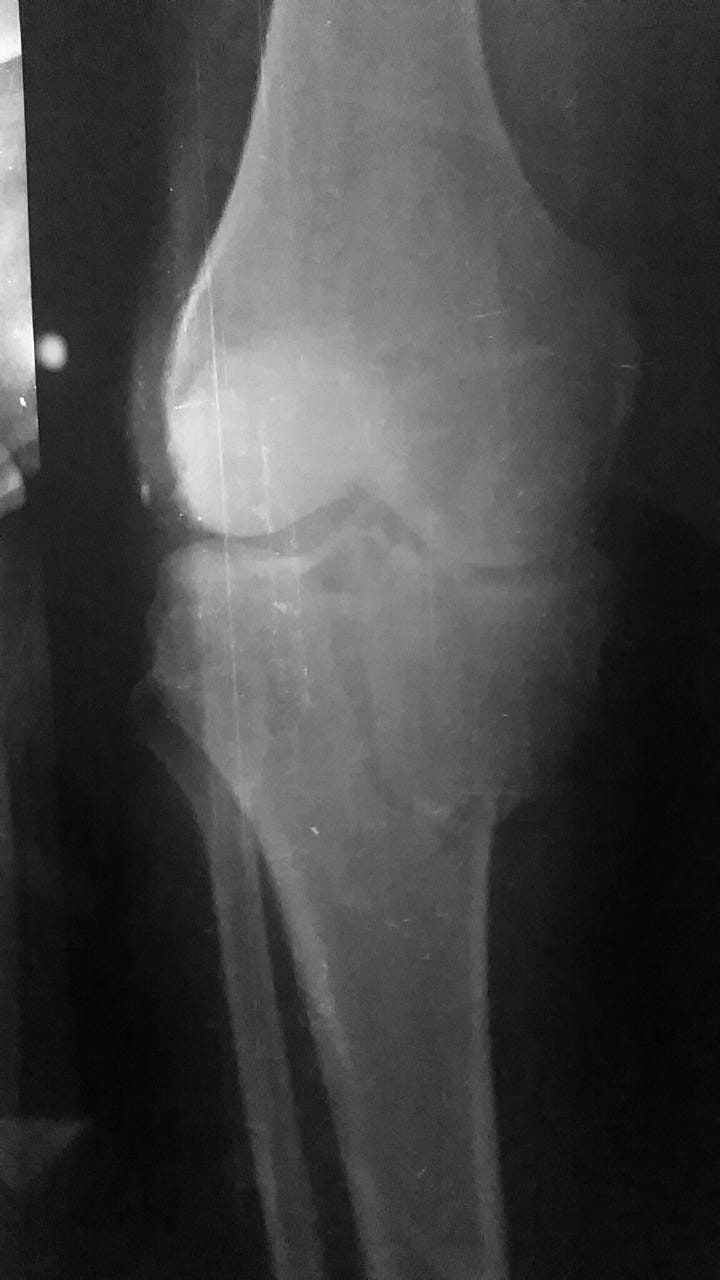

Patient had a knee fracture almost 4 months ago. But because of his exams approaching and his father's death followed by a liver transplant, a terrible mistake of no proper treatment was made. He was simply treated with traction and the patient can not straighten his leg now. Attached is the radio graph of his knee at the time of fracture. Just let me know if it can be treated?

The bony part may be relatively simple to treat with surgery. It will need a CT scan first. The bigger problem may be the untreated ligaments and meniscal injuries. I am sorry to say that the delay in treatment has made treatment very complex and results unclear. It needs proper evaluation. Because he is young and have a lifetime in front so surgical treatment to anatomically fix the malunited fracture may be the only good option.